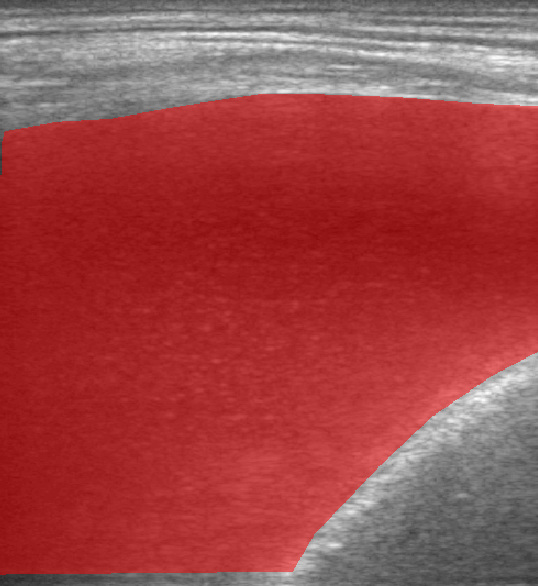

A total of 143 images were acquired from 59 patients. The images were obtained at the left and right PLAPS (PosteroLateral Alveolar and/or Pleural Syndrome) and subcostal views [4] with linear array and curved array (abdominal) ultrasound probes. The data were split according to the use of these probes into two datasets of 51 and 92 images, respectively for linear array and curved array. We denote these datasets as Dataset A (linear array) and Dataset B (curved array). All images were annotated at the time of acquisition to measure the extent of the effusion. These annotations consisted of small crosses at the top and bottom of the deepest area of effusion. See Figure 1 (left column) for example images.

Before being used for training and evaluating the models, each image was automatically cropped using a rectangular/cone mask to remove non-imaging content. Next, we applied an inpainting text algorithm using keras-ocr followed by template matching and edge detection algorithms from opencv to remove the annotations that were added to the images to measure the effusion. Examples of the outputs of this preprocessing are shown in Figure 1 (centre column).

All images in both datasets were manually segmented using the ITK-SNAP software [14] (www.itksnap.org) by a trained observer. Examples of ground truth segmentations are shown in Figure 1 (right column). These segmentations acted as ground truths for training and evaluating the proposed models. Additionally, a second trained observer performed independent segmentations of subsets of 10 random images each from the two datasets. These were used to compute an estimate of inter-observer variability in the manual segmentation process.

Qualitative prediction results of the two proposed models (baseline nnU-Net and nnU-Net with coordinate convolutions) on the two datasets are shown in Figure 2. Tables 1 and 2 summarise the quantitative performances in terms of DSC and area statistics. Histograms of the DSC values are shown in Figure 3. The median DSCs between the manual segmentations on the subsets of 10 images (i.e. the estimates of inter-observer variability) are also shown in Table 1.

It can be seen that, despite having fewer images, the baseline model for Dataset A obtained a higher median DSC than the model for Dataset B. For Dataset A the coordinate convolution model improved the DSC and reduced the area error and bias. In two-tailed Wilcoxon signed rank tests (0.05 significance) the difference between the baseline DSC and that of the coordinate convolution model was found to be statistically significant for Dataset A () but there was no statistically significant difference for Dataset B (). Interestingly, for both Dataset A and Dataset B, both the baseline and coordinate convolution models performed better than the estimate of inter-observer variability. However, we note that the inter-observer variability is quite high (i.e. median DSCs of 0.78 and 0.71), likely reflecting the difficulty and partly subjective nature of the effusion segmentation task. Therefore, it seems likely that the deep learning models are learning to segment effusion in the style of the main observer, which may not always be consistent with the second observer. In addition, the histograms shown in Figure 3 suggest that there are a significant number of failure cases in the outputs of both models (although fewer for the coordinate convolution model for Dataset A), again reflecting the difficulty of the task.

Rows 1-2: Dataset A. Rows 3-4: Dataset B.